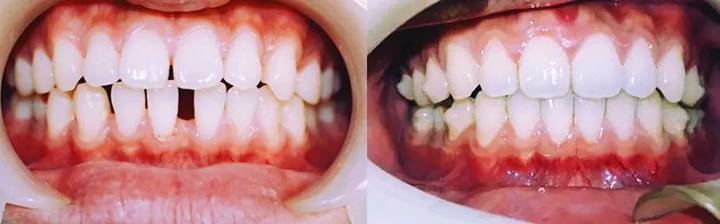

上图就是矫正前后牙齿的对比照,欢迎观看右边照片多一点!

那就是54副牙套带来的一口重生的白牙。

『 排齐上下前牙,关闭前牙散在间隙 』

——矫正目标临近达成,再有4副就能收工,完美!

完整的观察一下目前达到的矫治效果,会发现真的很棒!